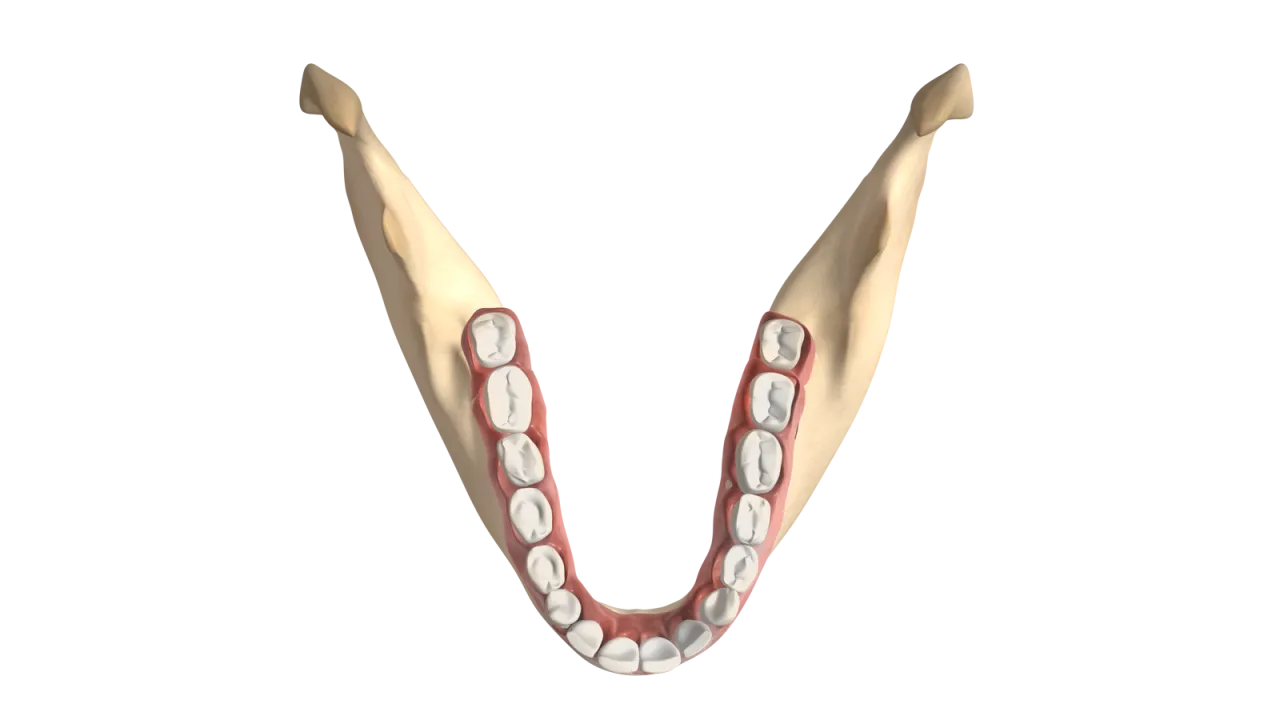

Zęby mądrości, powszechnie znane jako ósemki, to nic innego jak trzecie i ostatnie zęby trzonowe w naszych łukach zębowych. Znajdują się one na samym końcu, zarówno w szczęce, jak i w żuchwie. W idealnym scenariuszu, dorosły człowiek posiada cztery takie zęby po jednej ósemce w każdym z czterech kwadrantów jamy ustnej. To właśnie one są często bohaterami wielu dentystycznych historii, zarówno tych dobrych, jak i tych mniej przyjemnych.

Chcesz sprawdzić, czy masz ósemki i gdzie dokładnie się znajdują? To prostsze, niż myślisz! Wystarczy, że zaczniesz liczyć zęby od środka jamy ustnej, od jedynek, czyli siekaczy. Idąc wzdłuż łuku zębowego, w kierunku gardła, ósmy ząb, na który natrafisz, to właśnie ząb mądrości. Pamiętaj, aby policzyć je zarówno z prawej, jak i z lewej strony, na górze i na dole. Jeśli masz pełne uzębienie, powinieneś znaleźć po jednej ósemce w każdym rogu swojej jamy ustnej.

W gabinecie stomatologicznym rzadko usłyszysz o "ósemkach". My, dentyści, posługujemy się precyzyjnym, międzynarodowym systemem numeracji zębów, zwanym systemem Viohla. Dzieli on jamę ustną na cztery kwadranty, a każdy ząb ma swój unikalny dwucyfrowy numer. Pierwsza cyfra oznacza kwadrant, druga konkretny ząb. Dla zębów mądrości wygląda to następująco:

- 18: Prawa górna ósemka

- 28: Lewa górna ósemka

- 38: Lewa dolna ósemka

- 48: Prawa dolna ósemka